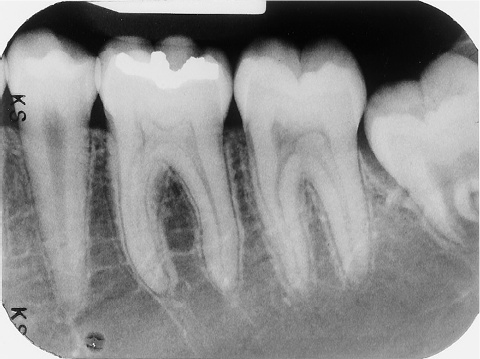

4 / 30

4. (Select ONE OR MORE correct answers)

The radiograph shows evidence of